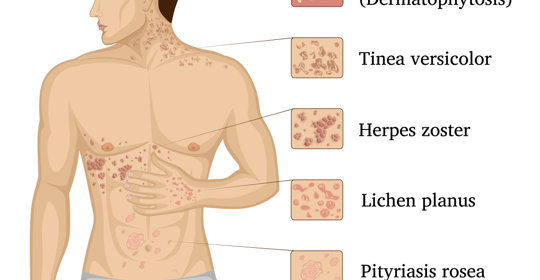

寶寶頭皮紅疹:頭皮結血痂,寶媽要這樣做!